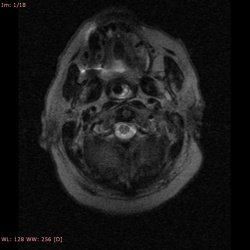

Мужчина 30 лет, в/в наркоман, ВИЧ инфекция.